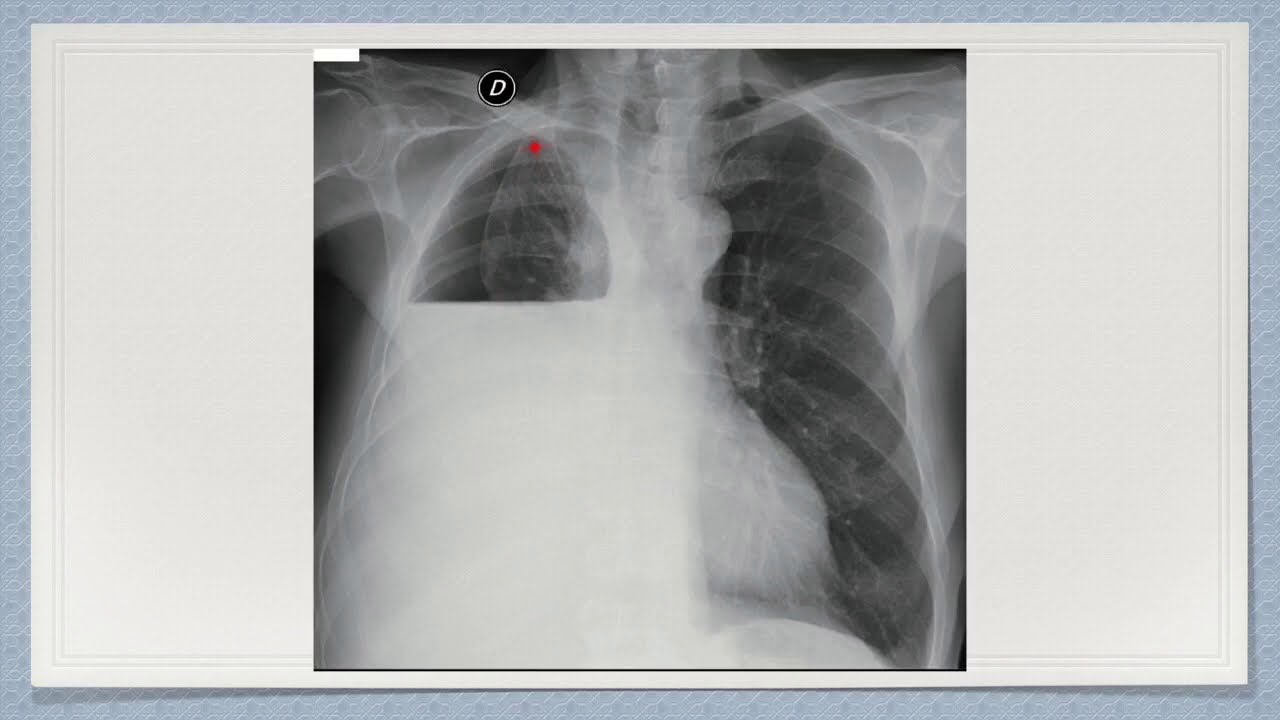

- Radiografía de tórax: Una radiografía de tórax puede mostrar líquido en el espacio pleural.

Aquí vemos el abordaje diagnóstico y terapeutico de un derrame pleural